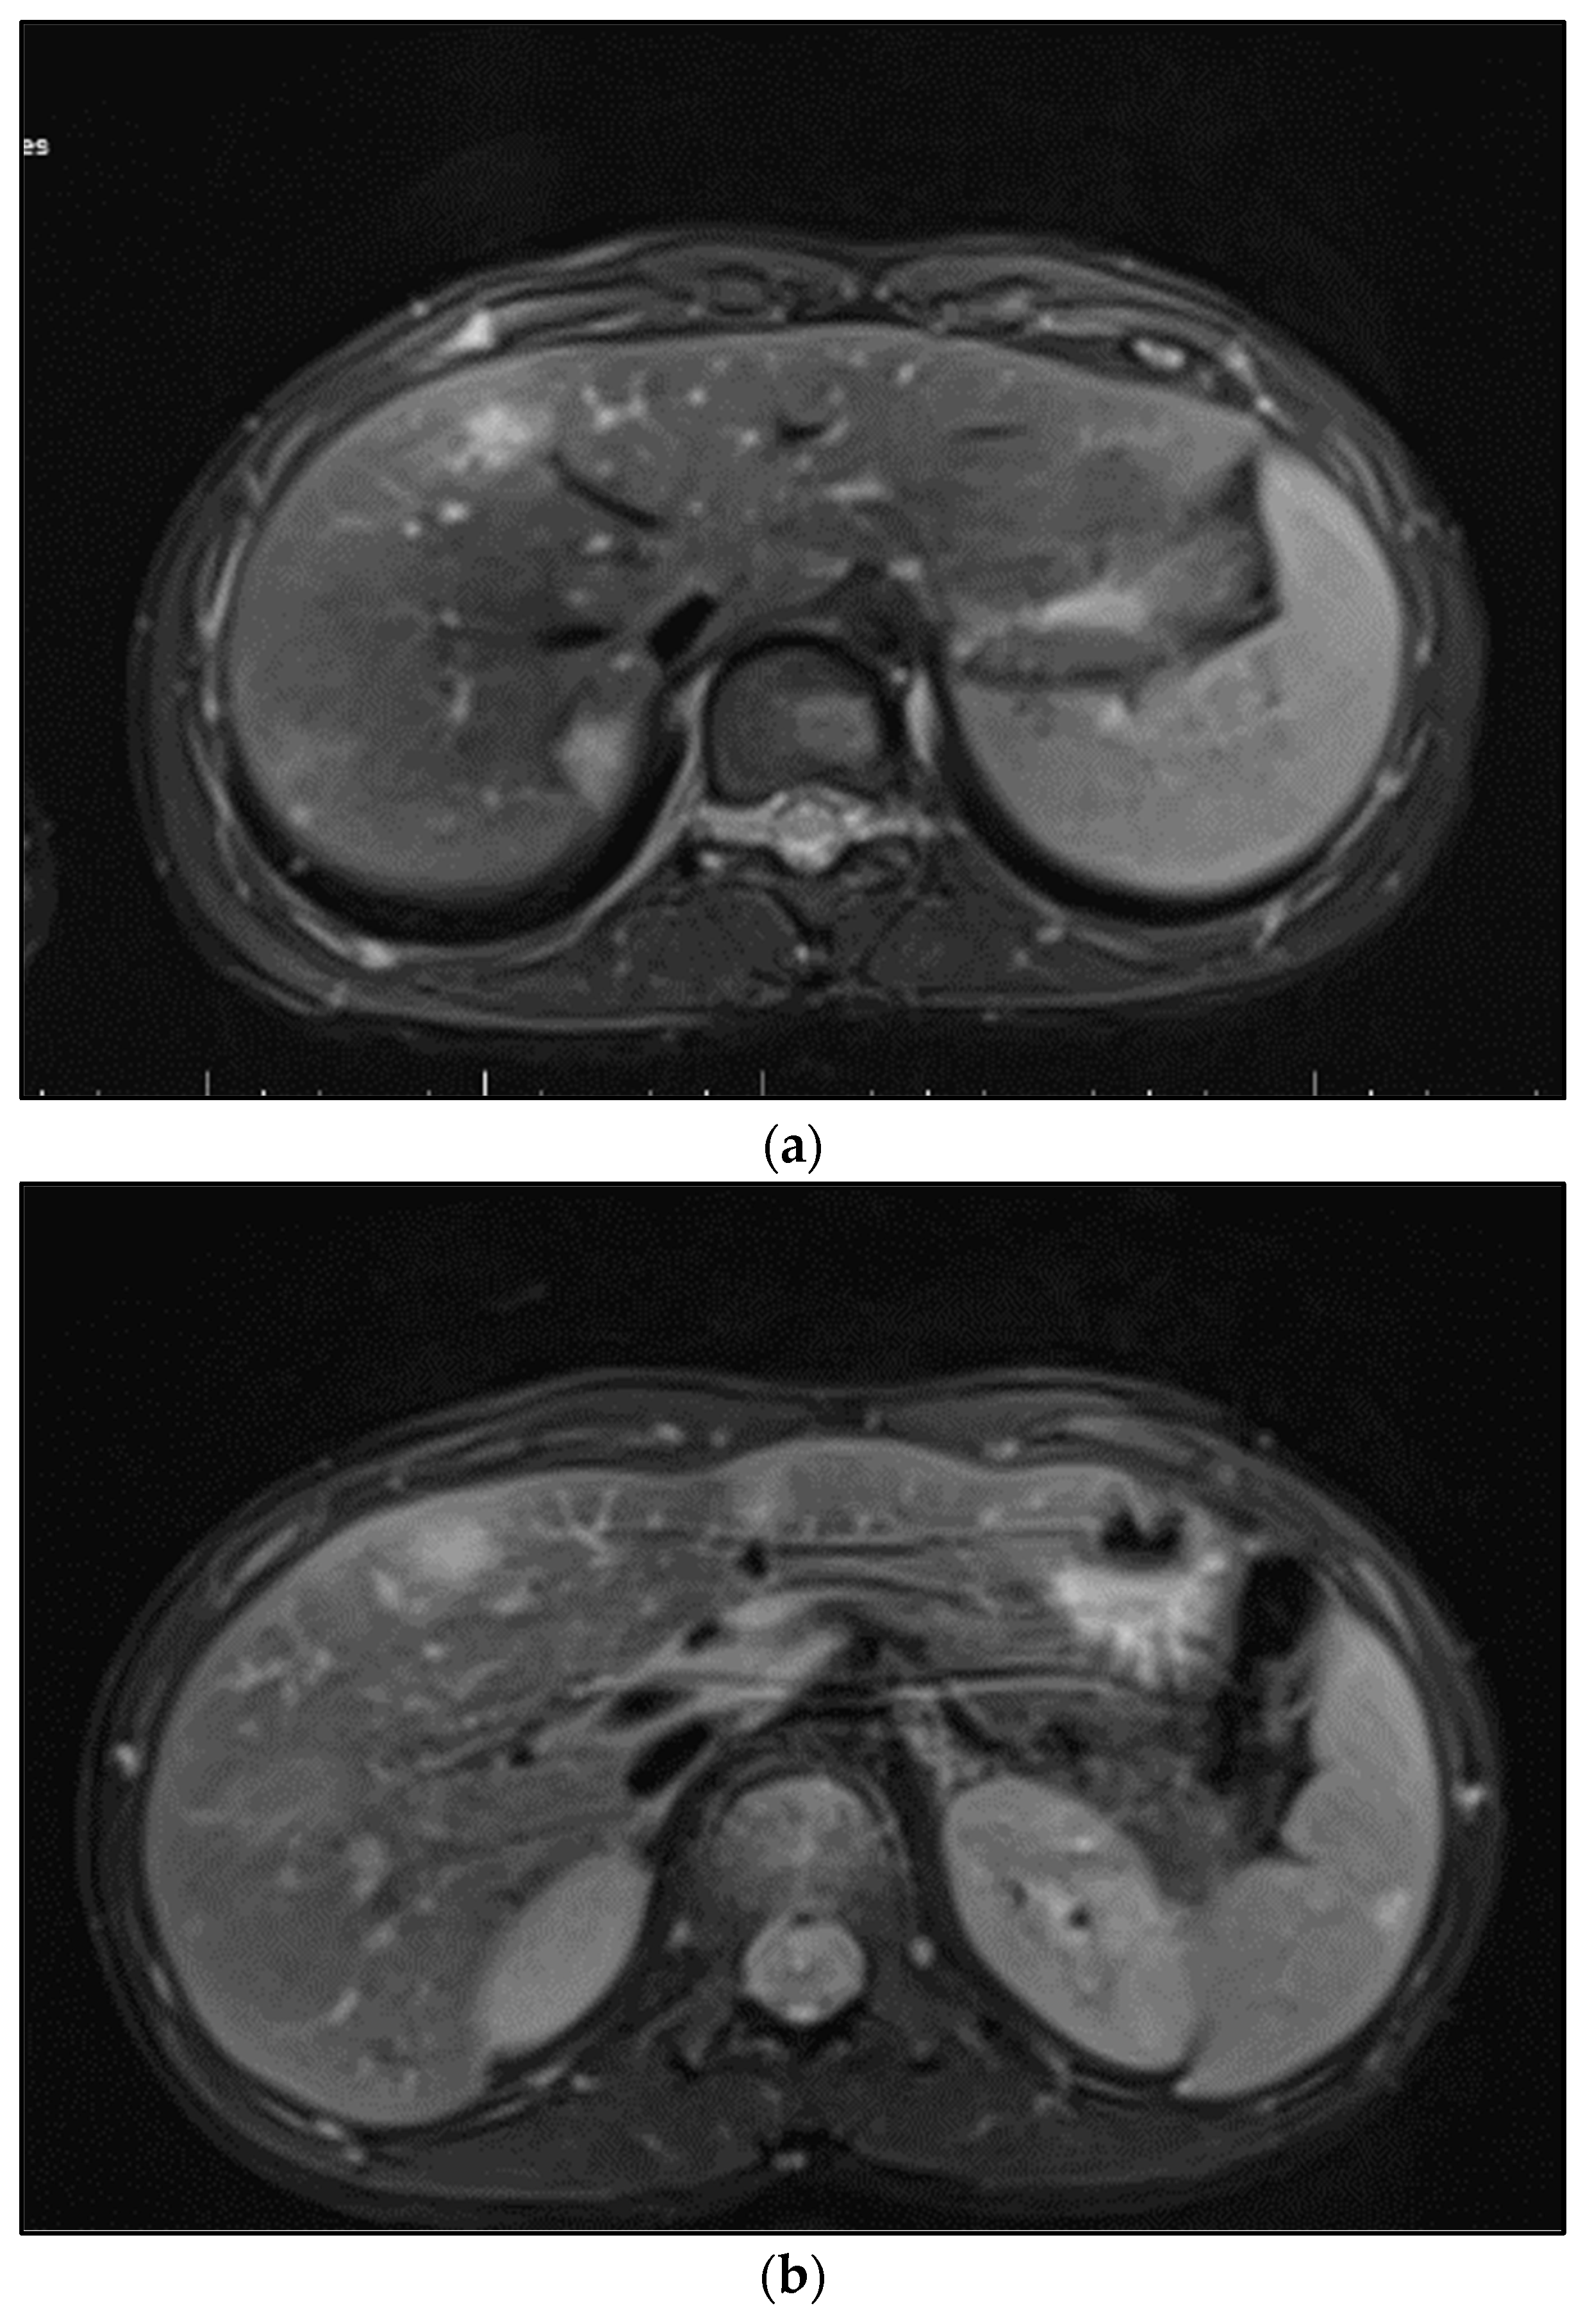

On imaging findings, we identified characteristic signs of systemic bartonellosis, as presented in Figure 2. The images revealed a profound impact of the infection across multiple organs. Specifically, Figure 2a demonstrates hepatic lesions that are distinguished by their central necrosis and surrounding diffuse edema, illustrating the severe effect of the infection on the liver. Figure 2b similarly depicts lesions within the spleen, following the same pattern of central necrosis enveloped by diffuse edema. These findings underscore the extensive reach of bartonellosis within the patient, affecting not only the liver and spleen but also extending to the skeletal system, including the right iliac bone, femoral neck, pubic bone, and L1–L2 vertebrae.

Figure 2. (a) Hepatic lesions with central necrosis and diffuse edema; (b) spleen lesions with central necrosis and diffuse edema.